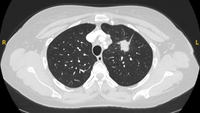

Cortes de tomografia computadorizada (TC) com exemplos de nódulos solitários semissólidos

Do acervo de Dr. George Tsaknis, MD, PhD, FRCP (Londres), MRQA, MAcadMEd, PGCert; usado com permissão